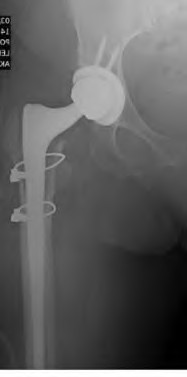

A 72-year-old female falls and sustains a periprosthetic femur fracture around her cementless total hip arthroplasty. Radiographs reveal a fracture extending just distal to the tip of the stem. The stem is radiographically loose, but there is excellent proximal and distal bone stock. According to the Vancouver classification, what is the fracture type and the recommended surgical treatment?

Explanation

A 75-year-old female sustains a fall 5 years after a cementless THA. Radiographs show a periprosthetic femur fracture occurring around the stem tip. Intraoperative assessment reveals the stem remains firmly fixed in the metaphysis, and the proximal bone stock is adequate. According to the Vancouver classification, what is the fracture type and the standard recommended treatment?

A 78-year-old female sustains a periprosthetic femur fracture 10 years after a cemented THA. Radiographs show a fracture around the tip of the stem with a loose femoral component and poor proximal bone stock, but adequate diaphyseal bone.

What is the most appropriate surgical treatment?

A 75-year-old female sustains a periprosthetic femur fracture around a cemented polished taper slip stem. Radiographs demonstrate a fracture around the tip of the stem. The stem is radiographically loose, but the proximal bone stock is excellent (Vancouver B2).

What is the gold standard surgical management?